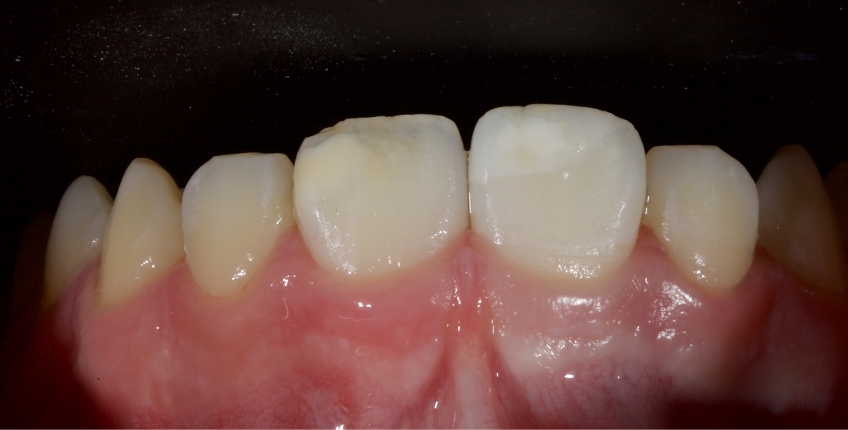

Case #2: Restoration With Direct Composite Resin

This 21-year-old male presented with an uncomplicated enamel-dentin fracture of the upper right central, lateral incisor, and canine following a fall.